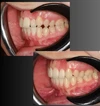

اعوجاج الأسنان

طبيب أسنان